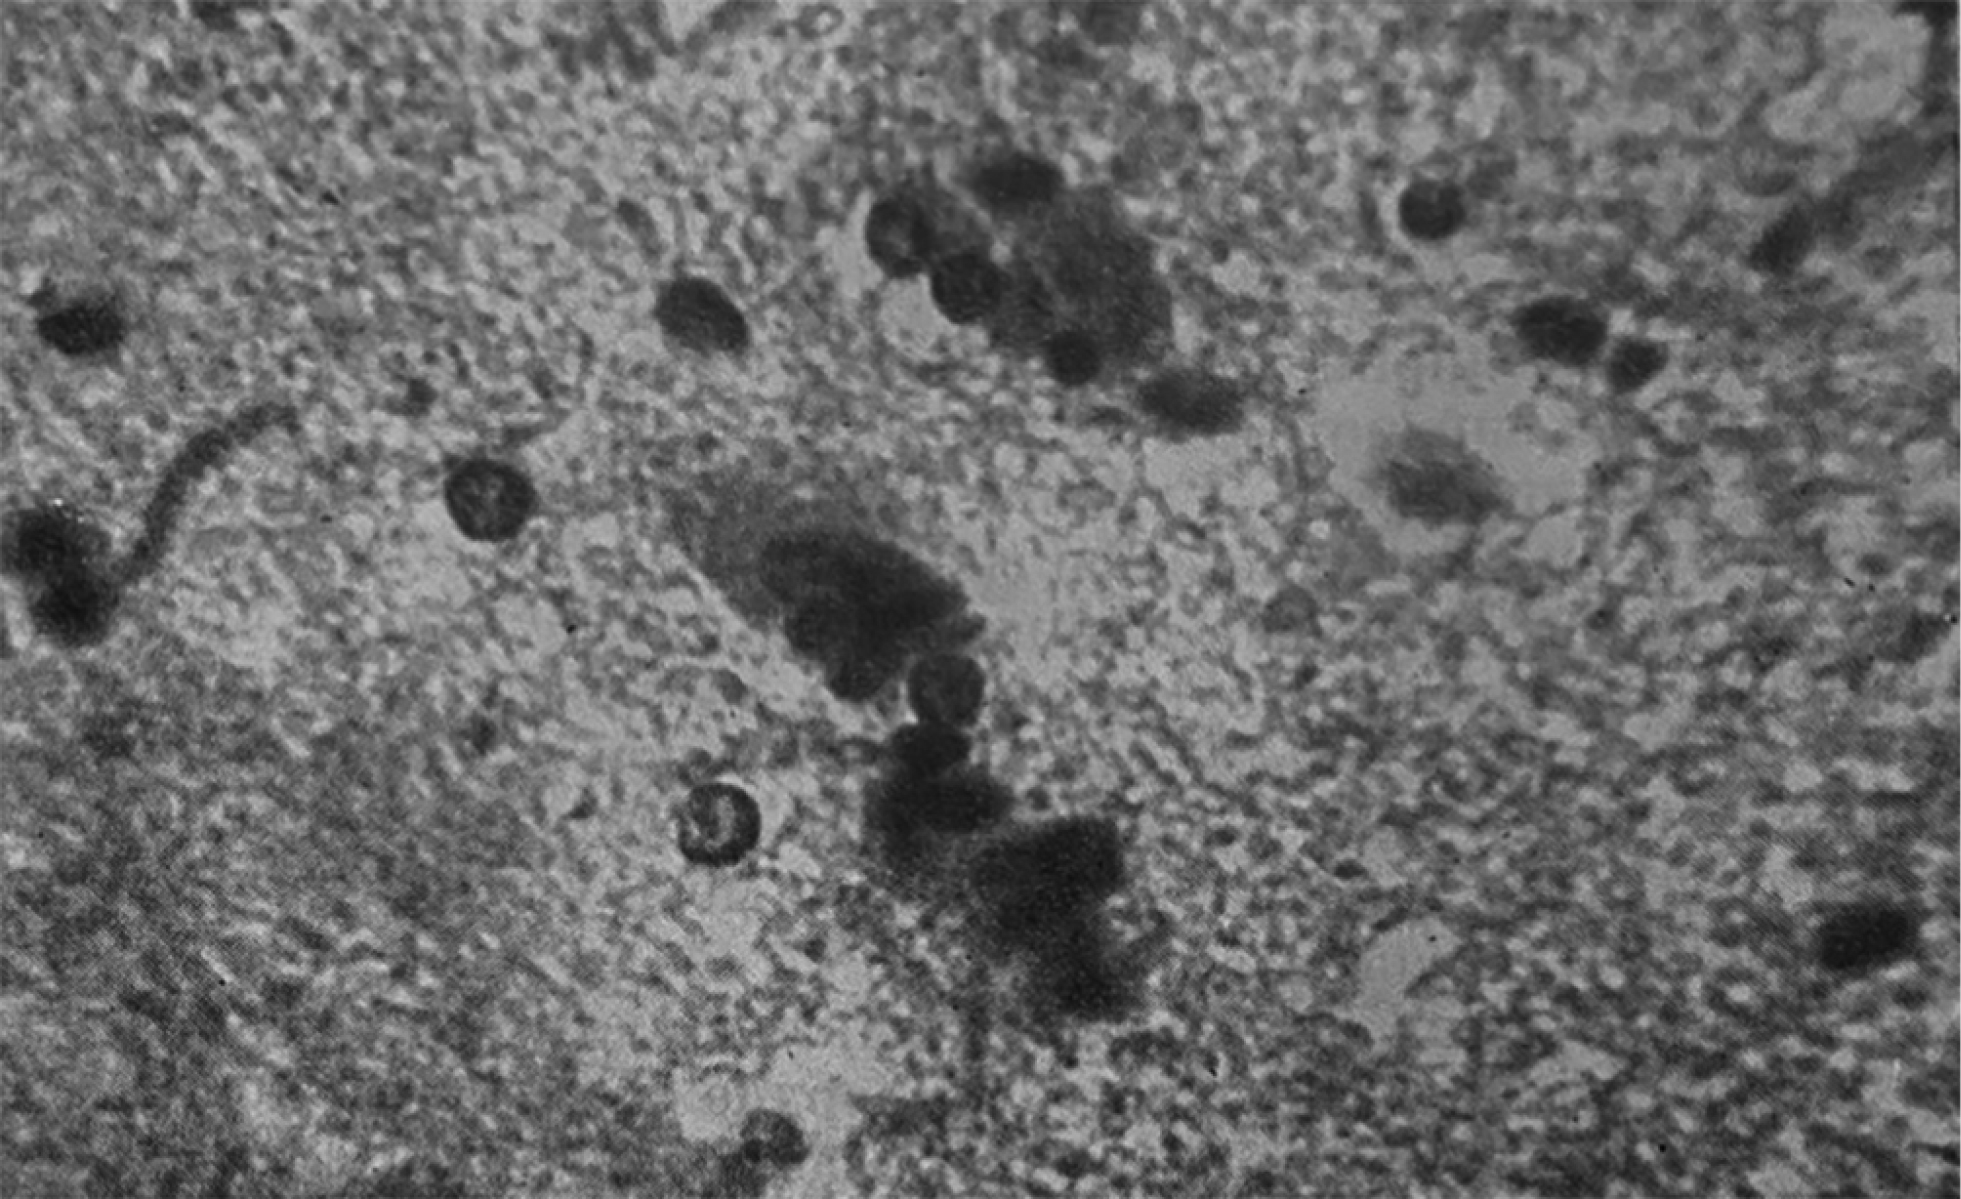

Среди работ Я.Л. Рапопорта по кардиопатологии особое место занимает изучение миокардитов и кардиомиопатий: он создал их систематику и дал клинико-морфологическую характеристику [6]. Он также ввёл в практику понятие реанимационной патологии. Лаборатория патоморфологии, которая располагалась на базе ИССХ АМН СССР, принимала активное участие в изучении пороков сердца, патологии искусственного кровообращения, перфузионных осложнений [3]. В монографии 1972 года [6] совместно с В.И. Бураковским, Г.Г. Гельштейном, Е.И. Степаняном и Г.И. Цукерманом Яков Львович Рапопорт на основе опыта 1300 операций, проведённых с использованием аппарата искусственного кровообращения, привёл первую отечественную классификацию осложнений, развивающихся во время операции с искусственным кровообращением и экстракорпоральной оксигенацией. Он занимался фундаментальными вопросами патоморфологических реакций организма на адекватность перфузии в ходе использования аппарата искусственного кровообращения (рис. 4). Большое значение Я.Л. Рапопорт придавал нарушению сосудистой и клеточной проницаемости как универсальным механизмам в патогенезе расстройств, возникающих в ходе длительного применения искусственного кровообращения. Я.Л. Рапопорт изучил гистологические изображения препаратов, полученных от экспериментальных животных; сосудов микроциркуляторного русла различной локализации: твёрдой мозговой оболочки, брюшины, перикарда, лёгких, миокарда и других. По результатам трёх серий экспериментов профессор Рапопорт и его коллеги пришли к выводу, что невозможно выявить ведущий механизм из аппарата искусственного кровообращения, наиболее значимо влияющий на патоморфологические изменения. Состав перфузата, объёмные скорости перфузии, длительность операции и принципы анестезии — всё в целом влияет на адаптационные изменения организма.

Рис. 4 . Микрофотографии из монографии [6]: a — периваскулярное кровоизлияние в лёгком при перфузии цельной кровью; b — контрактурные изменения пучков кардиомиоцитов.

Fig. 4. Microphotographs from the monograph [6]: a — perivascular hemorrhage in the lung during perfusion with whole blood; b — contracture changes in cardiomyocyte bundles.

Яков Львович Рапопорт предложил морфологическую систематизацию различных форм контрактурных сокращений мышечных пучков миокарда и изучил патологическую анатомию острой сердечной недостаточности [6]. Контрактурная дистрофия в рамках главы об острой сердечной недостаточности вследствие применения аппарата искусственного кровообращения рассматривается им как морфологический субстрат острой сердечной недостаточности (см. рис. 4). Статья Я.Л. Рапопорта и Ю.Г. Тинякова расширила представление об этом состоянии, разделяя некоторые морфологические понятия: в частности, авторы разделили собственно контрактуры, полосы сокращения, фрагментации и зернисто-глыбчатый распад [7].

Яков Львович Рапопорт также принимал участие в изучении морфологической реакции ЦНС, гематоэнцефалического барьера на гипоперфузию в ходе операций с использованием аппарата искусственного кровообращения (рис. 5).

Рис. 5. Нейронофагия при острой гипоксии мозга [6].

Fig. 5. Neuronophagia in acute cerebral hypoxia [6].